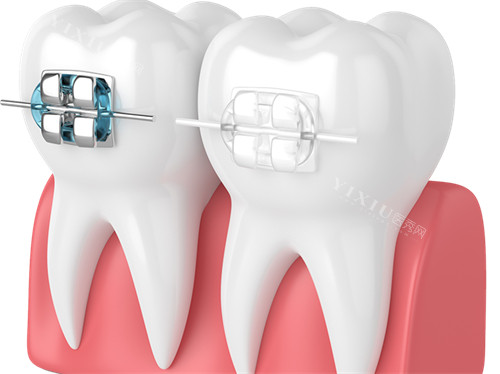

MBT 托槽,全称为 “美容正畸托槽”,是由正畸领域的三位骨干医生共同研发的成果。它的设计独具匠心,着重于减小摩擦力,以此提升牙齿移动的效率。其特殊的槽沟设计,就像是为牙齿量身定制的轨道,能帮助牙医更轻松地进行个性化矫治。无论是简单的牙齿不齐,还是复杂的矫正病例,MBT 托槽都能展现出出色的表现。

Roth 托槽

设计与原理

MBT 托槽以 “小摩擦” 为核心设计理念,就像给牙齿安装了一个顺滑的跑道,减小托槽与钢丝之间的摩擦力,促使牙齿能够快速矫正。而且,它的隐形设计,就像给牙齿穿上了一件隐形衣,受到许多追求美观的求美者的青睐。

Roth 托槽则重视托槽与钢丝间的紧密结合,通过强固的槽沟,如同给牙齿加上了精密的导航系统,使牙齿在矫正过程中实现严谨的转动与倾斜矫正。